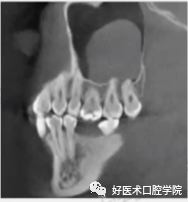

常见上颌窦底部,局部黏膜充血外渗膨胀,由于液体潴留在结缔组织而产生,呈微小的半球形或椭圆形,均匀而且不透明,CBCT和根尖周片显现明显,表现为上颌窦底的穹窿形,未被上皮包绕固称为假性囊肿,多被认为是牙源性感染导致,多可见因牙周病或根尖周病破坏的牙槽骨。

1)术前CBCT测量:术前测量上颌窦底壁到牙槽嵴顶距离、上颌窦底壁到囊肿边缘的距离以及测量设计骨开窗位置。